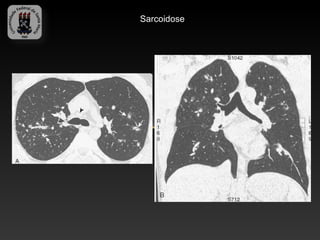

-SARCOIDOSE

-Doença idiopática caracterizada por granulomas não caseosos.

-Envolvimento pulmonar bilateral é o habitual e a linfadenopatia é a manifestação

intratorácica mais comum.

-Cerca de 10% tem radiografia de torax normal.

-Infecção sobreposta é responsável por uma significativa morbidade e mortalidade.

-Achados da TC:

-   Linfadenopatia (75-80%), calcificações em casca de ovo

-   Áreas de atenuação em vidro fosco

-   Nódulos subpleurais e perivascular

-   Espessamento irregular peribroncovascular e dos septos interlobulares

-   Predomínio nas regiões médias e superiores

-   Fibrose – complicação tardia

Sarcoidose